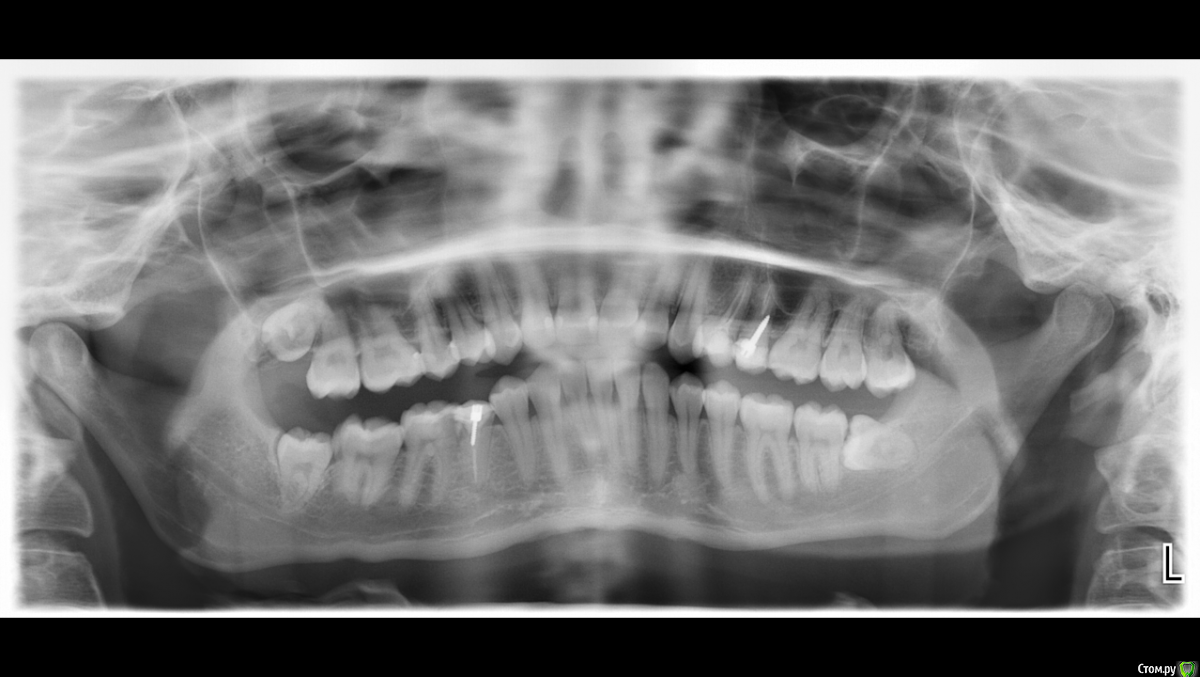

Alnetta Опубликовано 16 января, 2016 Поделиться Опубликовано 16 января, 2016 Здравствуйте! Скажите, пожалуйста, можно ли спасти зуб, который находится сверху 4й сзади справа (на снимке)? Кстати, как он называется?)Если, уже не спасти, и придется удалять, каким способом посоветуете вставить новый зуб? Не хотелось бы, чтобы соседние зубы пострадали.Через какое время после удаления можно новый вставлять? Так же интересует, последний снизу зуб справа (на снимке), он меня никак не беспокоит и никогда не беспокоил, нужно ли его удалять? Я девушка, мне 24. Заранее спасибо за ответы. Ссылка на комментарий

Korel Опубликовано 16 января, 2016 Поделиться Опубликовано 16 января, 2016 можно ли спасти зуб, который находится сверху 4й сзади справа (на снимке)? Какой?) http://s014.radikal.ru/i329/1601/fe/c8da6cb8a766.jpg 18 и 38 удалять (Называются моляры)) состояние 25 и 45 (премоляры) по этому снимку фифти-фифти, надо делать прицельные. Ссылка на комментарий

DmitrySH Опубликовано 16 января, 2016 Поделиться Опубликовано 16 января, 2016 Да, сложно сказать по снимку, и как сказали выше - судьба зуба 25 - 50/50Потеря премоляров бывает очень кстати, если требуется ортодонтическое лечение. Ссылка на комментарий